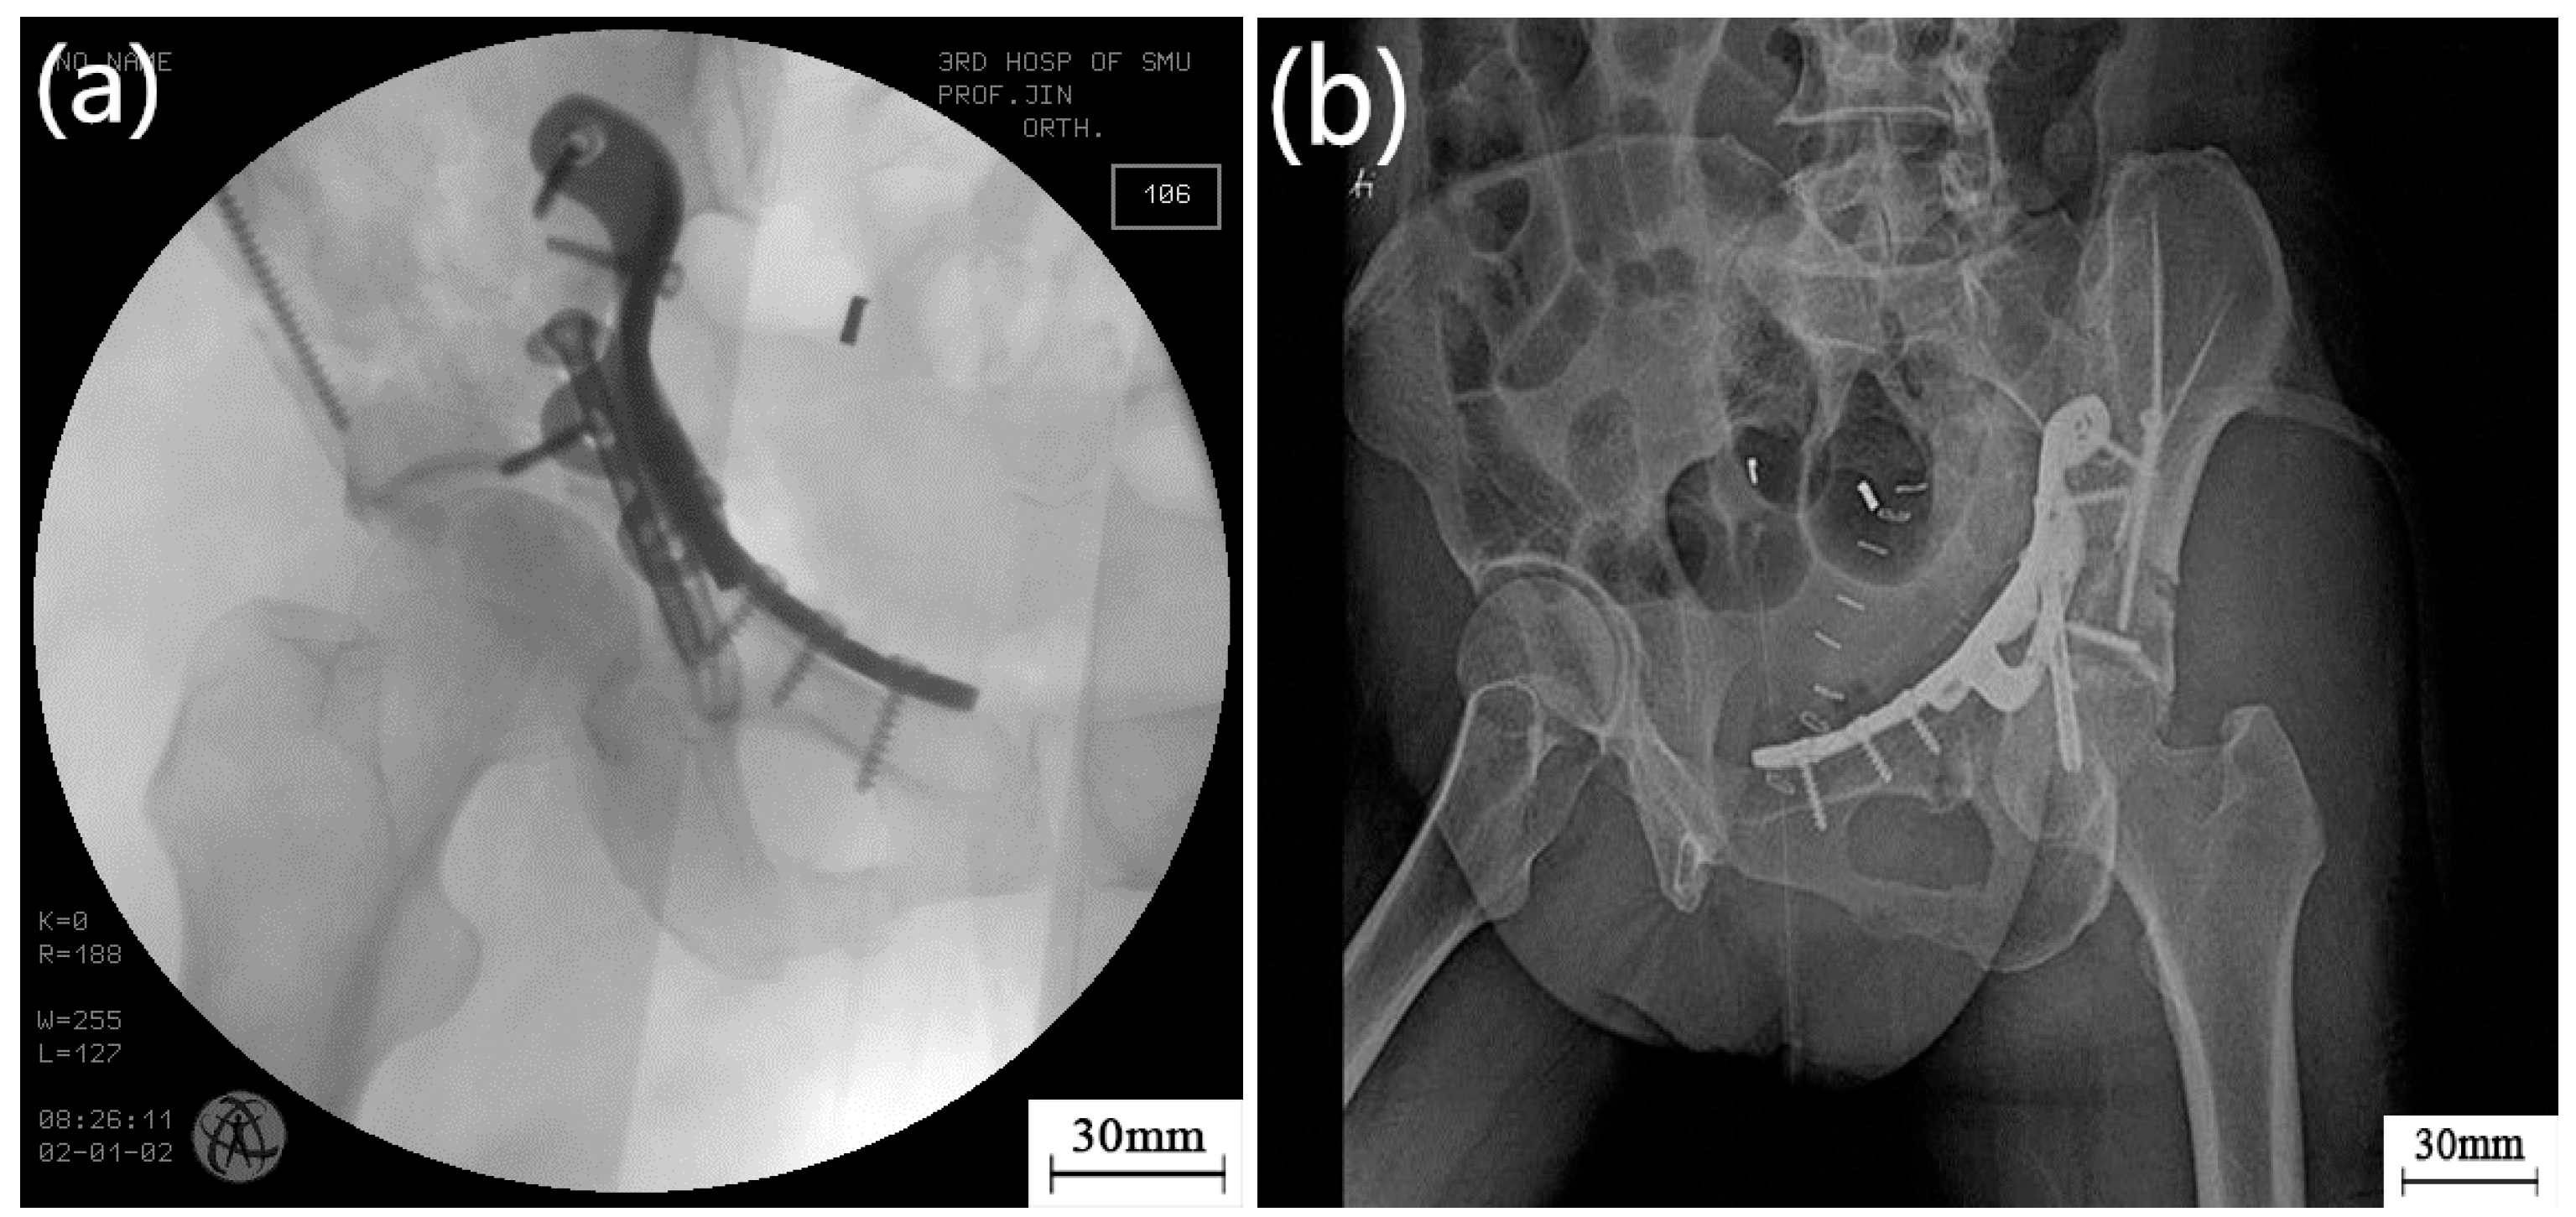

- The customized bone plate was used in a clinical operation. Matching of the customized bone plate and broken pelvis was confirmed by intra operative C-arm and X-ray imaging following surgery, which not only fixed the broken bone blocks, but also guided pelvis restoration. Operating time was reduced to about 2 h.